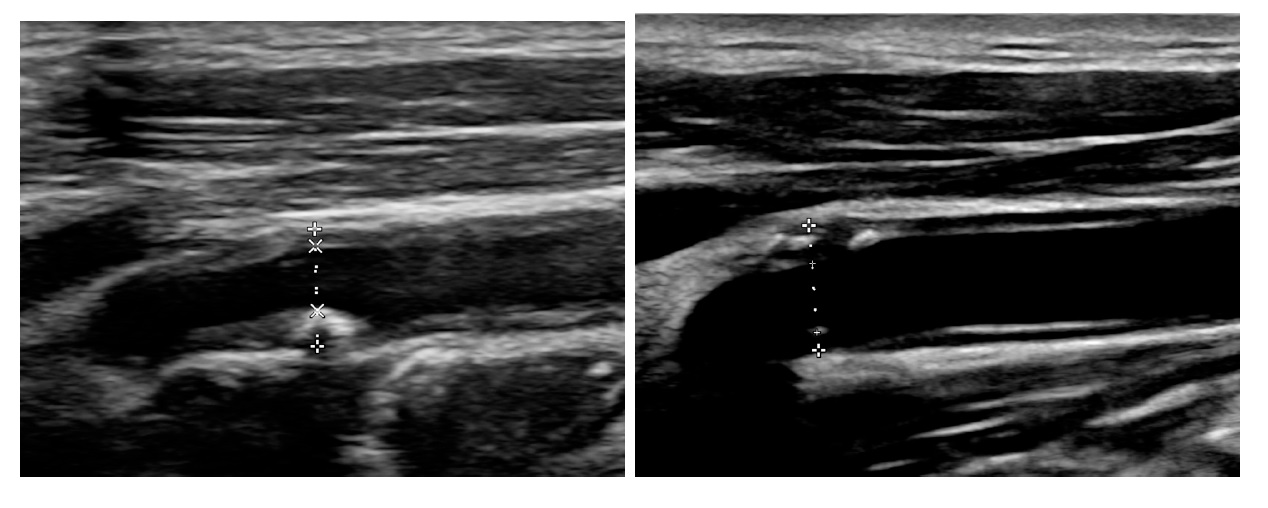

不過,隨著病情進展,財伯需仰賴鼻胃管進食、氣切管呼吸,黃正昇醫師遂轉介雁行合作團隊為恭居家護理所,將財伯轉換為重度居家醫療照護階段,偕同雁行夥伴饒芸僑居家護理師,提供居家醫療及護理之雙重照護。